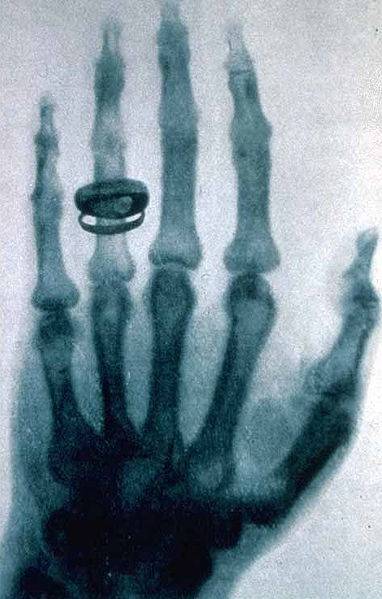

医学影像是指为了医疗或医学研究,对人体或人体某部分,以非侵入方式取得内部组织影像的技术与处理过程。它包含以下两个相对独立的研究方向:医学成像系统(medical imaging system)和医学图像处理(medical image processing)。前者是指图像行成的过程,包括对成像机理、成像设备、成像系统分析等问题的研究;后者是指对已经获得的图像作进一步的处理,其目的是或者是使原来不够清晰的图像复原,或者是为了突出图像中的某些特征信息,或者是对图像做模式分类等等。